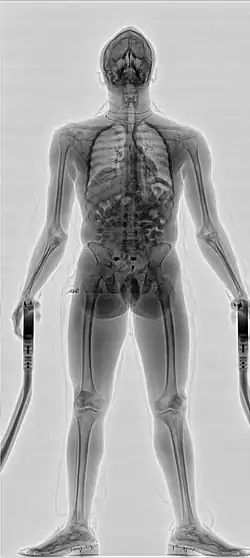

- Сканеры персонального досмотра, основанные на технологии проникающего рентгеновского излучения.[6] В этих сканерах рентгеновское излучение проходит сквозь тело человека и затем улавливается детектором или линейкой детекторов. Этот вид сканеров персонального досмотра позволяет обнаружить объекты, спрятанные не только под одеждой, но и внутри тела человека (например, перевозимые наркокурьерами в желудке наркотики) или в его естественных полостях. Полученная доза составляет в районе 0,25 μSv и в основном регулируется американским стандартом по радиационной безопасности для систем персонального досмотра, использующих гамма- или рентгеновское излучение ANSI 43.17.2009[7]. Существуют модификации в рентгенозащитной кабине, позволяющей исключить воздействие отражённого излучения на персонал и окружающих людей. Можно выделить одно- и двух проекционные сканеры, позволяющие одной проекцией получить снимок всего тела, а второй проекцией получить снимок определённых областей (например, области живота), представляющих интерес с точки зрения поиска сокрытых предметов. Обычно сканирование по второй проекции происходит на большей дозе и является уже не стандартной процедурой, а углублённым досмотром подозрительного субъекта, проводимой выборочно и обычно по подозрению сотрудников служб.